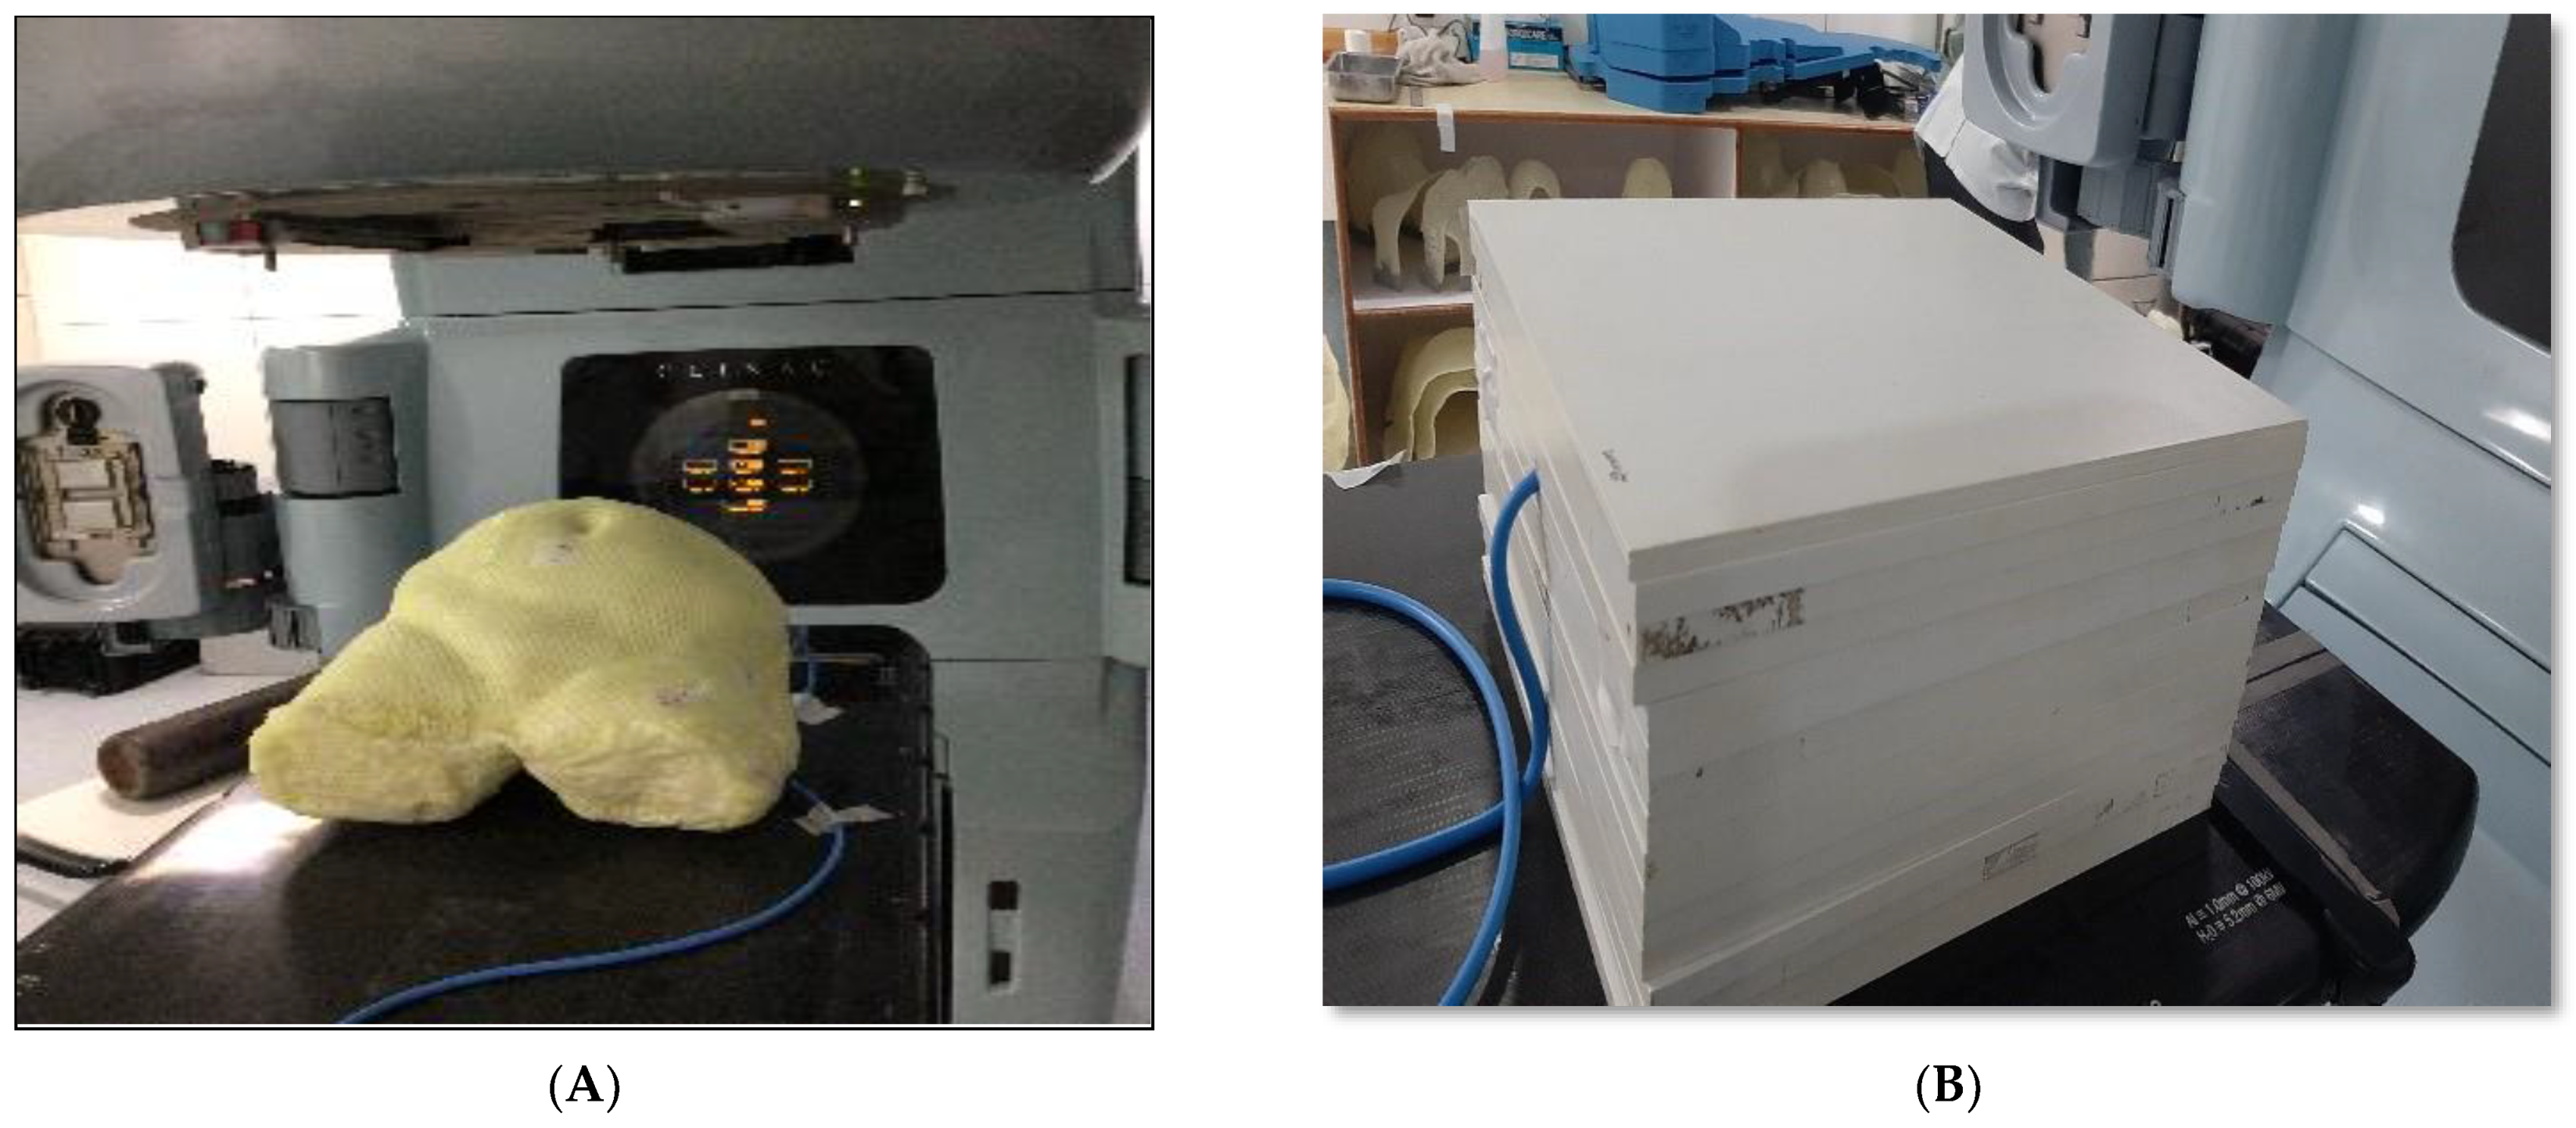

2.1. Phantom Design

2.2. Fabrication of Phantom